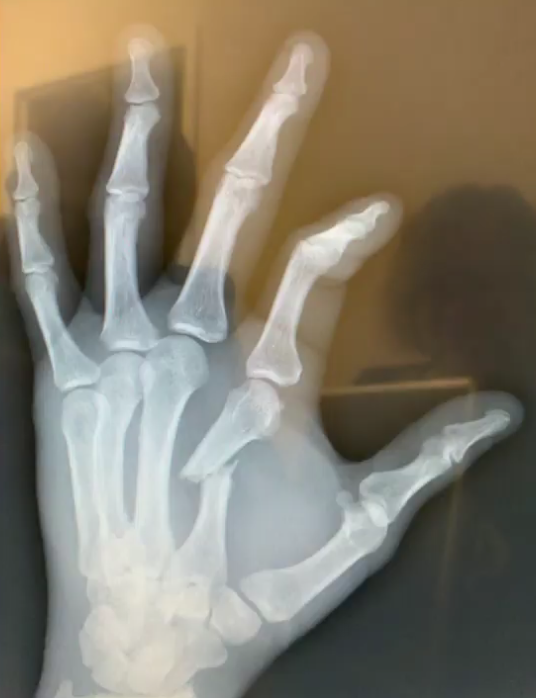

Anthony Smith braut á sér höndina í bardaganum gegn Alexander Gustafsson á laugardaginn. Smith fer í aðgerð í vikunni og verður frá í nokkra mánuði.

Smith fór í myndatöku í gær og er höndin nokkuð illa brotin. Smith fer í aðgerð á höndinni á miðvikudag og mun taka fjóra mánuði fyrir höndina að jafna sig. Smith býst því við að taka sér tvo mánuði í að koma sér aftur af stað þegar höndin hefur jafnað sig og mun hann því ekki berjast næsta hálfa árið.